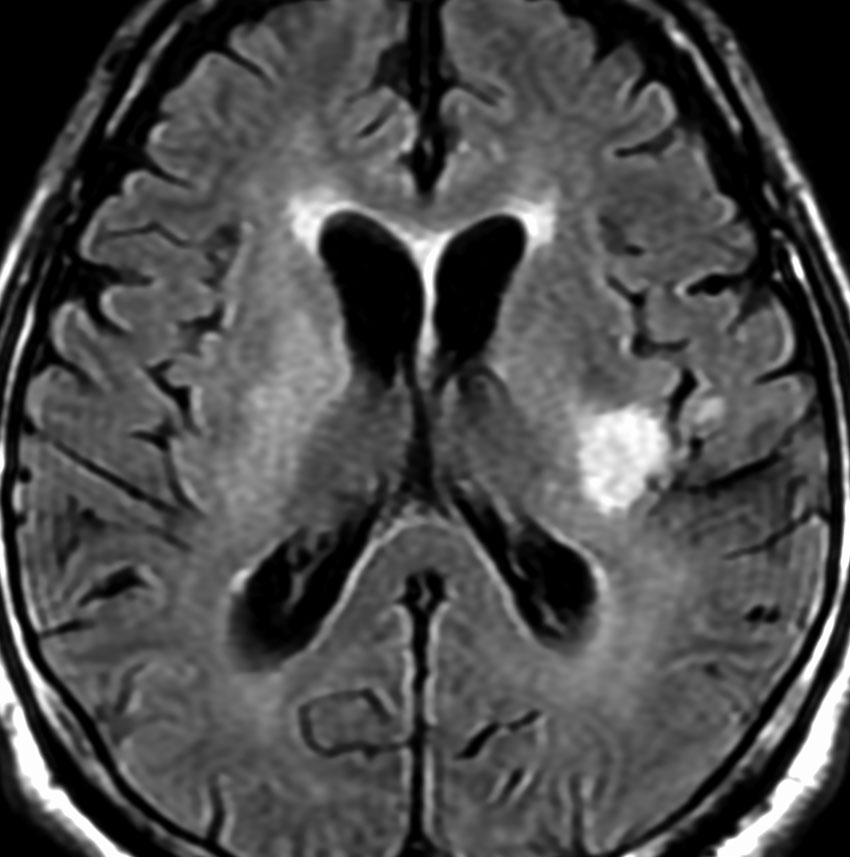

MRI画像所見 60代で嚥下障害と構音障害で発症した例

延髄から中脳まで腫瘍があって脳幹部が腫れています。この画像ですと,小児のびまん性橋膠腫(DIPG,びまん性正中グリオーマ)のように見えます

両側視床から大脳基底核,両側大脳半球深部白質,脳梁まで広範囲に腫瘍が存在します。退形成性星細胞腫のようにまだらにガドリニウム増強されます。